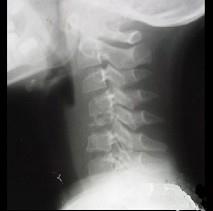

问题 男,37岁,主诉颈部疼痛,活动时加重,休息后疼痛可减轻,夜间盗汗等,请结合所提供图像,选出最佳答案 ( )

选项 A、颈椎结核 B、骨髓瘤 C、颈椎骨转移 D、颈椎退行性变 E、骨巨细胞瘤

答案 A